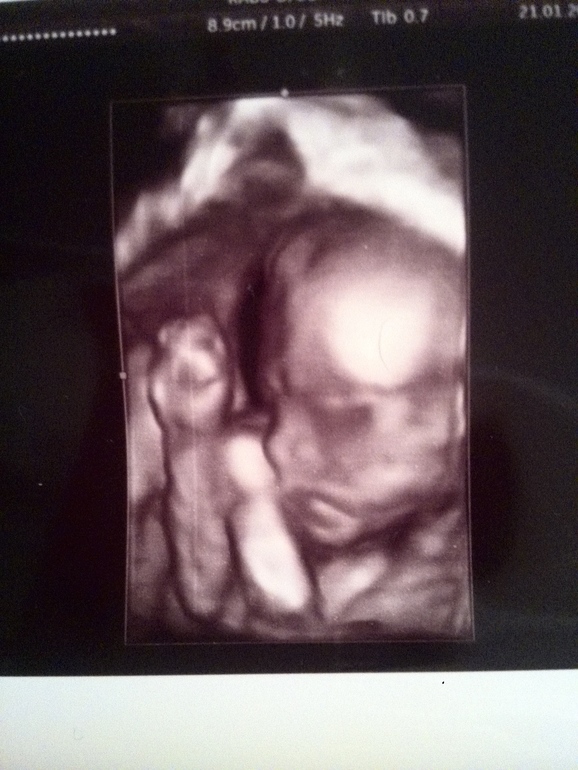

Моя малышка 22 недельки)

Малыш, до и после родовВчера была на УЗИ, развивается хорошо ( только маленькая сказали) может зависит от набора веса тоже моего? В первую б +20кг, а в эту сейчас +3кг. Я не переживают, малышка сильная и с 14 дней чувствую перекаты, а с 16 пиночки и толчки. Сейчас конкретные танцы в животе. Вчера на УЗИ врач минут 10 не мог её споймать, чтобы поменять печень. То снизу головка, через секунду сверху, потом поперёк. Несколько раз пытался сфоткать в 3д, она ручками закрывается, хмурит бровки. Потом начала глотать воды, потом сладко позевала, а потом сосала пальчики) при этом дрыгала ножками)) единственное - кровоток слабый в маточных артериях. Но узист мне прямо сказал, чтоб я не переживала и это все не страшно, и следующее узт в 30 недель с допплером. Я то пойду раньше))) а вот и моя сладкая)))

хочу следующее узи тоже в 3д сделать.так личико видно хорошо. а я ещё ни разу не пробовала.